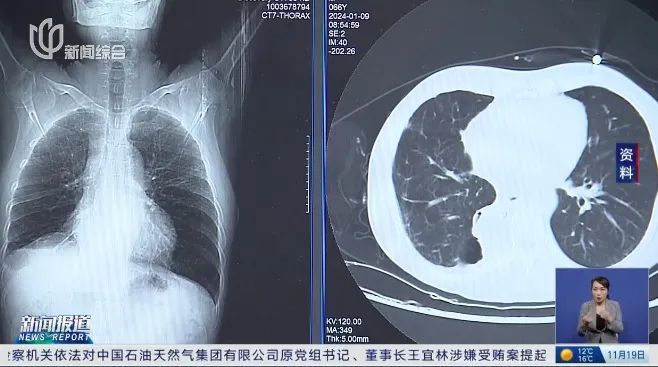

2020年,张女士查出肺部磨玻璃结节。一年后,张女士入职一家外资公司,公司为她购买了重大疾病责任险。

2023年2月,张女士确诊为肺癌,后入院手术治疗。术后,她向保险公司申请理赔,却遭到拒赔。

当时医生说我是纯磨玻璃结节,我那个时候才二十多岁,也没有肿瘤家族史。医生给我的意见就是肺结节不等于肺癌,让我随访观察就好。

法院审理后认为,保险公司没有明确把磨玻璃结节作为疾病的一种进行规定,根据通常的医学诊疗标准,张女士投保时所检查出的磨玻璃结节,不构成医学上的疾病。

投保之前,并没有哪一份诊疗记录显示被保险人被检查出来的磨玻璃结节,具有恶化或者需要手术的情况。因此,法庭认定更多意义上还是一种体征,并不能认为是构成医学上所指的疾病。